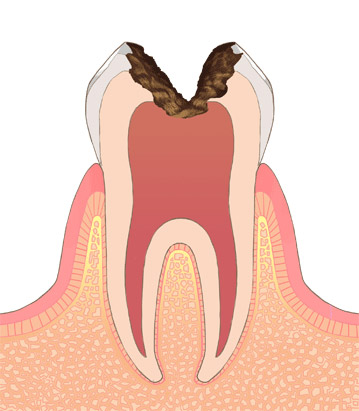

むし歯が象牙質の内側の歯髄に達したものです。この段階では、歯髄に細菌が進入し激しい痛みを伴うことがあります。

歯髄を取り除き、中の消毒。歯髄の出入り口まで薬で塞ぎ、保存する処置を行います。